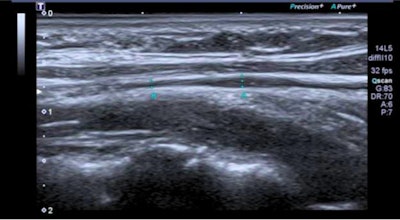

Spanish research has found possible links between long COVID and vagus nerve dysfunction in patients. Ultrasound images show (Above) longitudinal section of the left vagus at the cervical level, where there is a slight fusiform thickening, and (Below) an axial cut of left cervical vagus showing hyperechogenic perineural thickening. Images courtesy of Dr. Gemma Lladós et al.However, the researchers said the mechanism that causes long COVID is currently unknown. Therefore, Lladós et al wanted to determine the morphological and functional activities of the vagus nerve in their pilot study of long-COVID patients with dysfunction, using ultrasound and functional tests.

Six patients had mild vagus nerve thickening and higher echo on neck ultrasound scans. Thoracic ultrasound, meanwhile, showed flattened diaphragmatic curves in 10 patients. Ten out of 16 patients also showed reduced maximum inspiratory pressures.

"Radiologists may find by ultrasound in the lateral cervical area some images over the vagus nerve reflecting mild reactive inflammatory changes," Lladós said. "In addition, a flattened diaphragmatic curve visualized by chest ultrasound could translate into decreased diaphragmatic mobility during respiration."